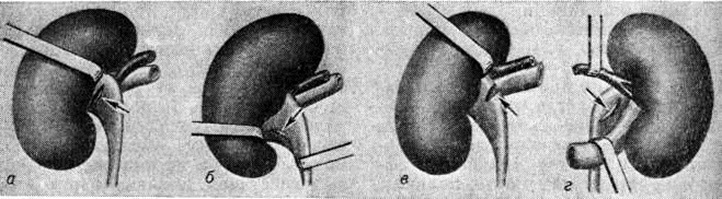

При Почечнокаменная болезнь выполняют следующие виды операций: пиелолитотомию, пиелокаликолитотомию, нефролитотомию, каликотомию, резекцию почки, нефростомию (смотри полный свод знаний) и нефрэктомию (смотри полный свод знаний). Применяют различные виды пиелолитотомии (рисунок 9). Наиболее широко используется задняя продольная или поперечная пиелолитотомия, при небольших лоханках этот разрез выполняется субкортикально. Нижнюю пиелолитотомию рекомендуют при внутрипочечных лоханках, верхне-поперечную пиелолитотомию применяют редко. Передняя пиелолитотомия показана преимущественно при аномалиях формы и положения почек. После удаления камня большинство урологов считает целесообразным ушивать наглухо разрез лоханки кетгутом.